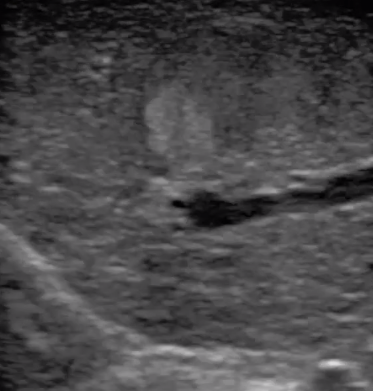

3  腹腔鏡超聲探頭

腹腔鏡超聲是超聲技術(shù)和腹腔鏡技術(shù)的融合,腹腔鏡超聲降低了對超聲探測深度的要求。由微小切口進入手術(shù)部位,多角度彎曲可選擇,降低手術(shù)難度及風險;與受檢組織器官直接接觸,有效避免氣體干擾。

應用科室:麻醉科、手術(shù)室、普外科、泌尿外科、婦產(chǎn)科、腫瘤科、介入科等

腹腔鏡下 肝臟占位